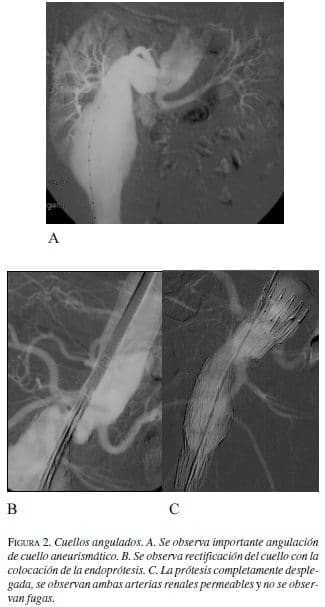

Se define como el ángulo formado entre el cuello aórtico proximal y el eje longitudinal principal del aneurisma. El eje del aneurisma se define como la línea que va desde la porción proximal del aneurisma, o extremo distal del cuello proximal, hasta la bifurcación ilíaca. Se clasifica en leve cuando va de 0 a 30º, moderada cuando es de 30-60º, y severa cuando es mayor de 60º. La angulación del cuello proximal puede ser perjudicial cuando supera los 50º y cuando es mayor de 60º, generalmente se considera una contraindicación relativa para el tratamiento endovascular.

El Cómite Endoluminal de la Sociedad de Cirugía Vascular / Sociedad Internacional de Cirugía Cardiovascular recomienda angulaciones máximas en el cuello de 120 grados (figura 2).

Los cuellos angulados deberán ser sometidos a una serie de pruebas para conocer su comportamiento. Mediante la colocación de las guías rígidas y/o introductores para estimar su corrección. Se recomienda el uso de prótesis de fácil desplazamiento y con fijación suprarrenal.

En estos casos es conveniente que el cuello tenga una longitud superior a los 15 mm, porque sin duda se perderá parte del mismo durante las maniobras de soltura al hacerlo de forma asimétrica.

También es muy importante controlar la posición de las arterias renales, porque en estos casos es difícil de visualizar su origen correcto. En general los cuellostienen dos desplazamientos: anterior o lateral; éstos últimos son más fácilmente corregibles.